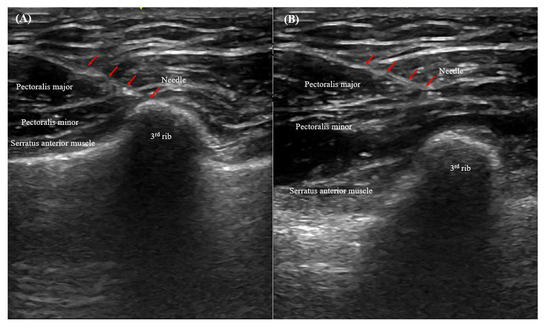

2.5. Ultrasonography-Guided PECS II